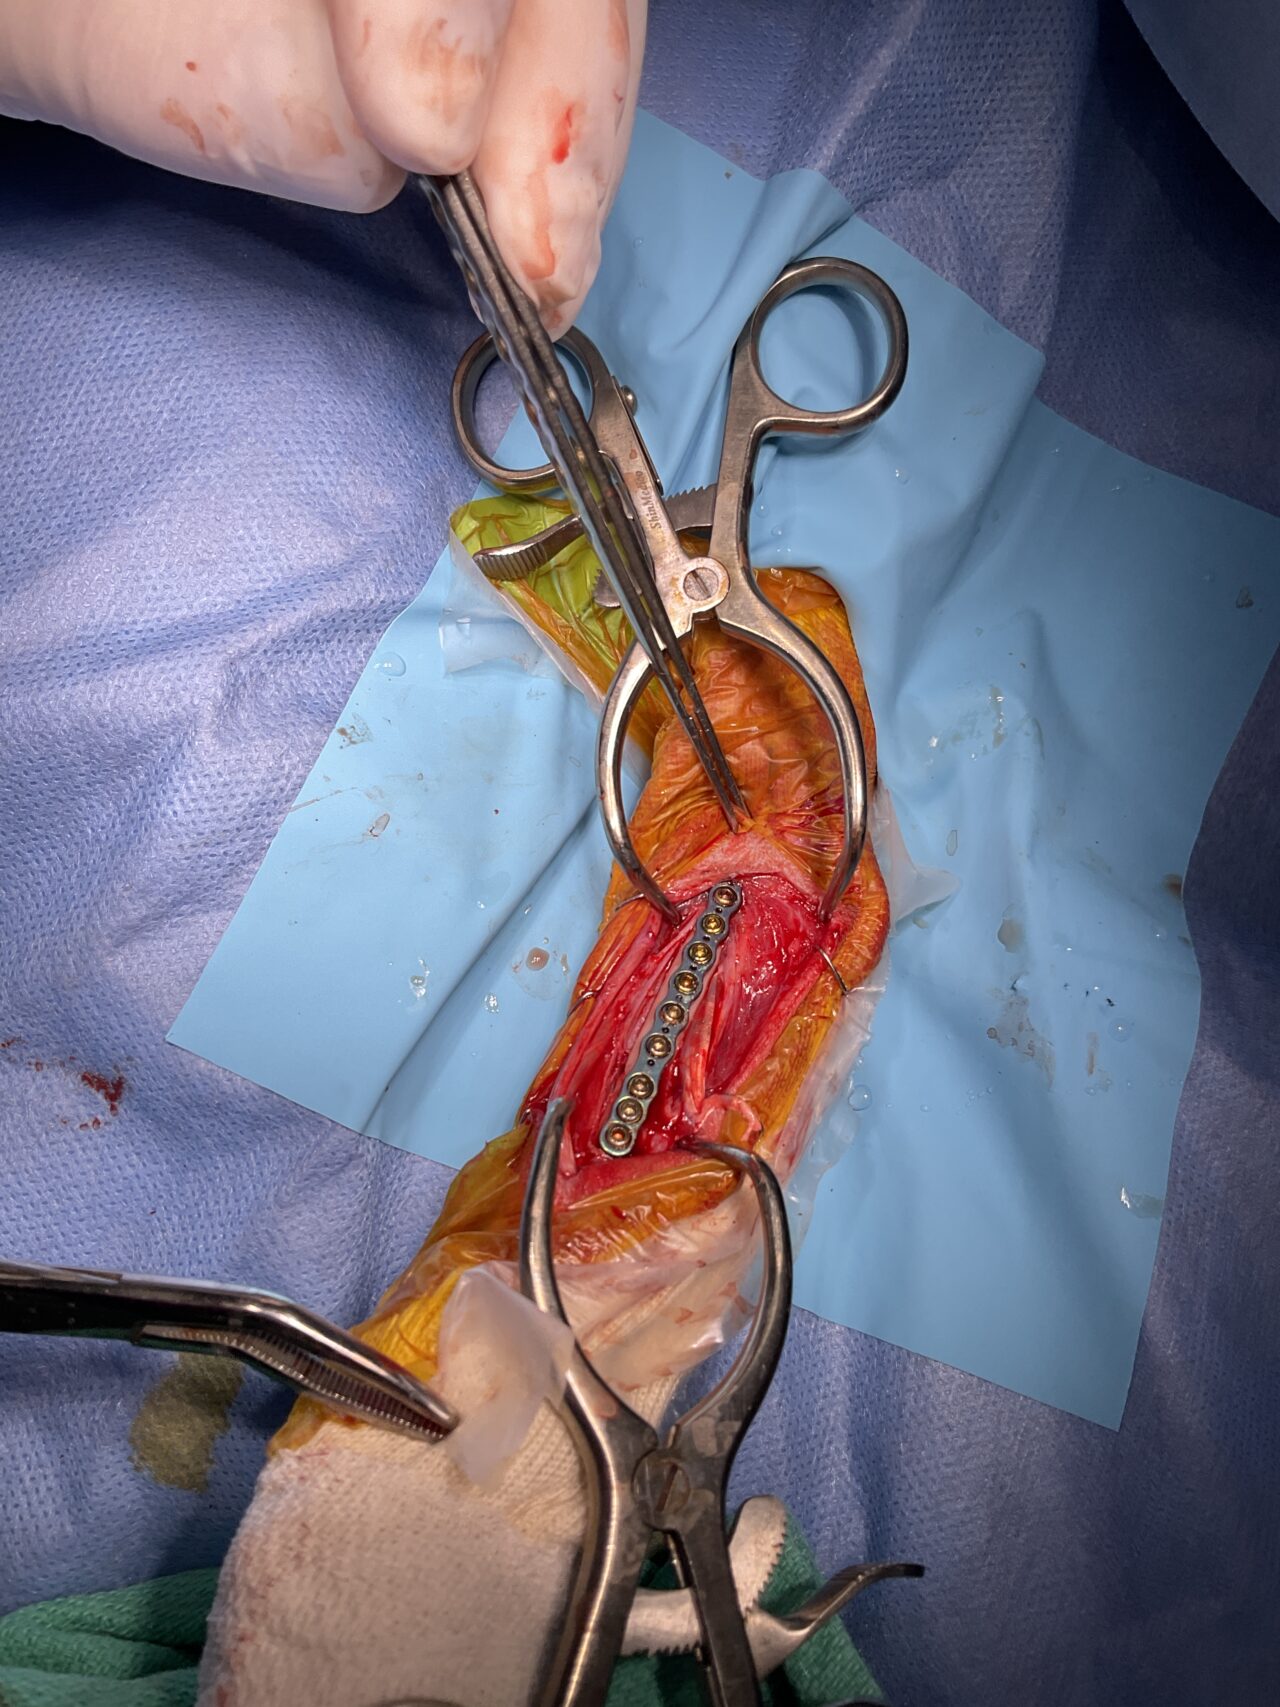

橈骨固定術 #249 Toy Poodleさんがソファーからジャンプして橈骨骨折をしたとのことで主治医の先生から固定術の依頼がありました。1.5 Titanium Locking Plateで固定術を行いました。しばらくは安静が必要です。 症例カテゴリー 放射線治療整形外科軟部組織外科脳神経外科内科腫瘍外科救急・集中治療リハビリテーション科腫瘍内科内視鏡科脳神経科呼吸器外科中医・漢方猫の腎移植循環器科